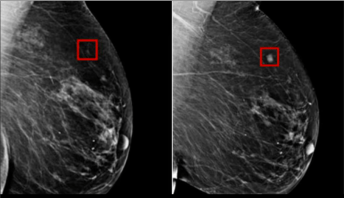

Exciting developments are taking place in the healthcare industry, driven by advancements in technology, particularly in the field of AI and computer vision. Recent studies have shown great promise for the use of AI in the early detection of cancer, achieving impressive accuracy rates of up to 94%. This technology can also be applied in other areas such as drug discovery, personalized medicine, and disease prevention. Beyond healthcare, AI and computer vision can be used to improve road safety, monitor crops, and optimize yield in the agriculture industry, and more. John Deere, for example, has incorporated AI and computer vision technology into its agricultural equipment to help farmers optimize their yields and reduce waste. While there are still challenges to overcome, such as ensuring that AI algorithms are trained on diverse and representative datasets, the future of healthcare looks promising with these technological advancements. #AIinHealthcare #ComputerVision #CancerDetection